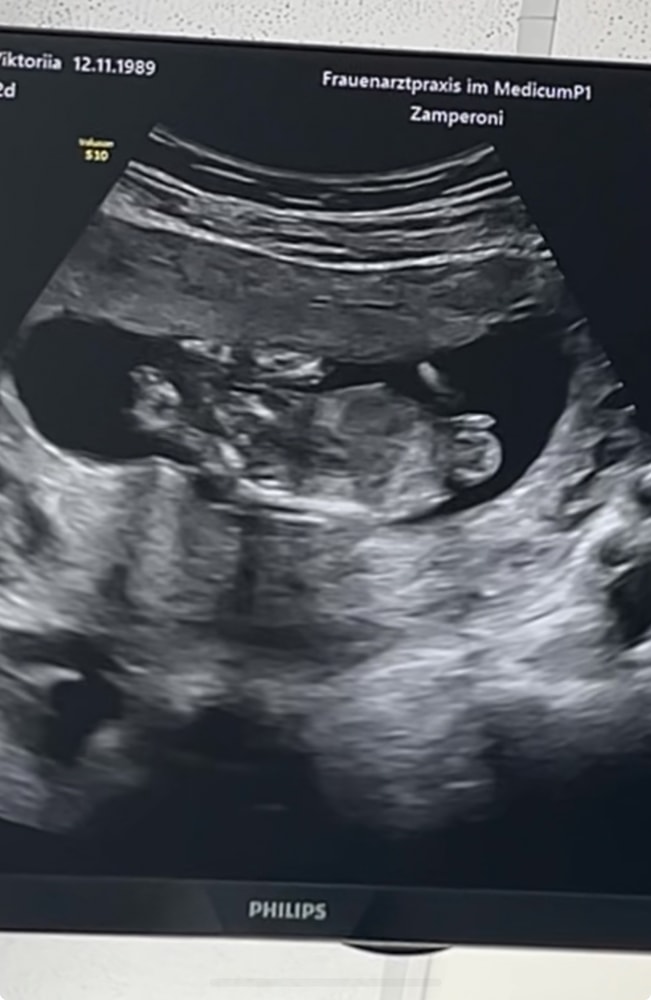

13 недель + 2 дня

Пол малышаСходила на узи, все в порядке 🙏 дали даже видео записать мужу 🥹 теперь это моё любимое видео. ♥️

Сдала кровь на нипт + оплатили что б узнать пол. Хотим бабушке рассказать, и что б знать кто там 🙈

на кого похоже? А то я смотрю многие гадают по фото узи …